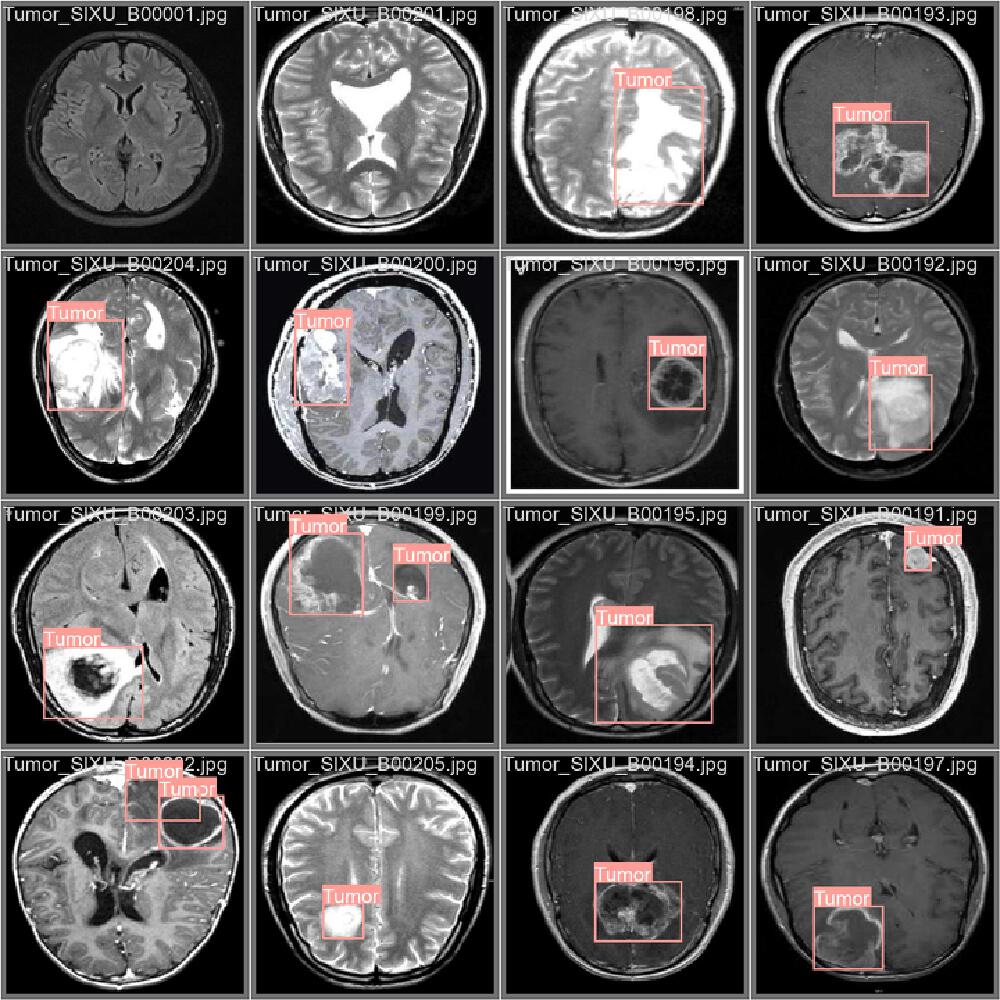

医疗诊断:脑肿瘤检测准确率达96.6%

在医疗影像领域,YOLOv5已成为辅助诊断的重要工具。基于YOLOv5的脑肿瘤检测系统在3076张MRI/CT图像数据集上实现96.6%的mAP值,F1-Score达0.93,将医生初筛时间从30分钟缩短至5分钟。

如上图所示,多张脑部MRI扫描图像中用红色矩形框标注了"Tumor"(肿瘤)区域,展示了YOLOv5模型对脑部肿瘤的检测结果。这种可视化检测结果能帮助医生快速定位病灶,提高诊断效率和准确性。

该系统支持图片、视频和实时摄像头输入,通过PySide6构建的用户界面直观展示检测结果,包含热力图、类别标记和统计分析等高级功能。在实际临床应用中,早期癌症检出率提升15%,为患者争取了宝贵的治疗时间。